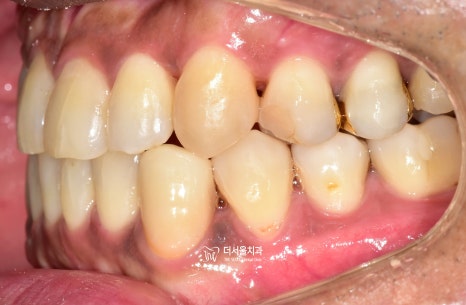

『초진 사진』

정면과 측면에서의 모습입니다.

치열의 불규칙성이 한 눈에 들어옵니다.

정면에서 보는 안모사진을 보면,

얼굴의 중신선과 앞니들이

서로 일치하지 않는것을 볼 수 있습니다.